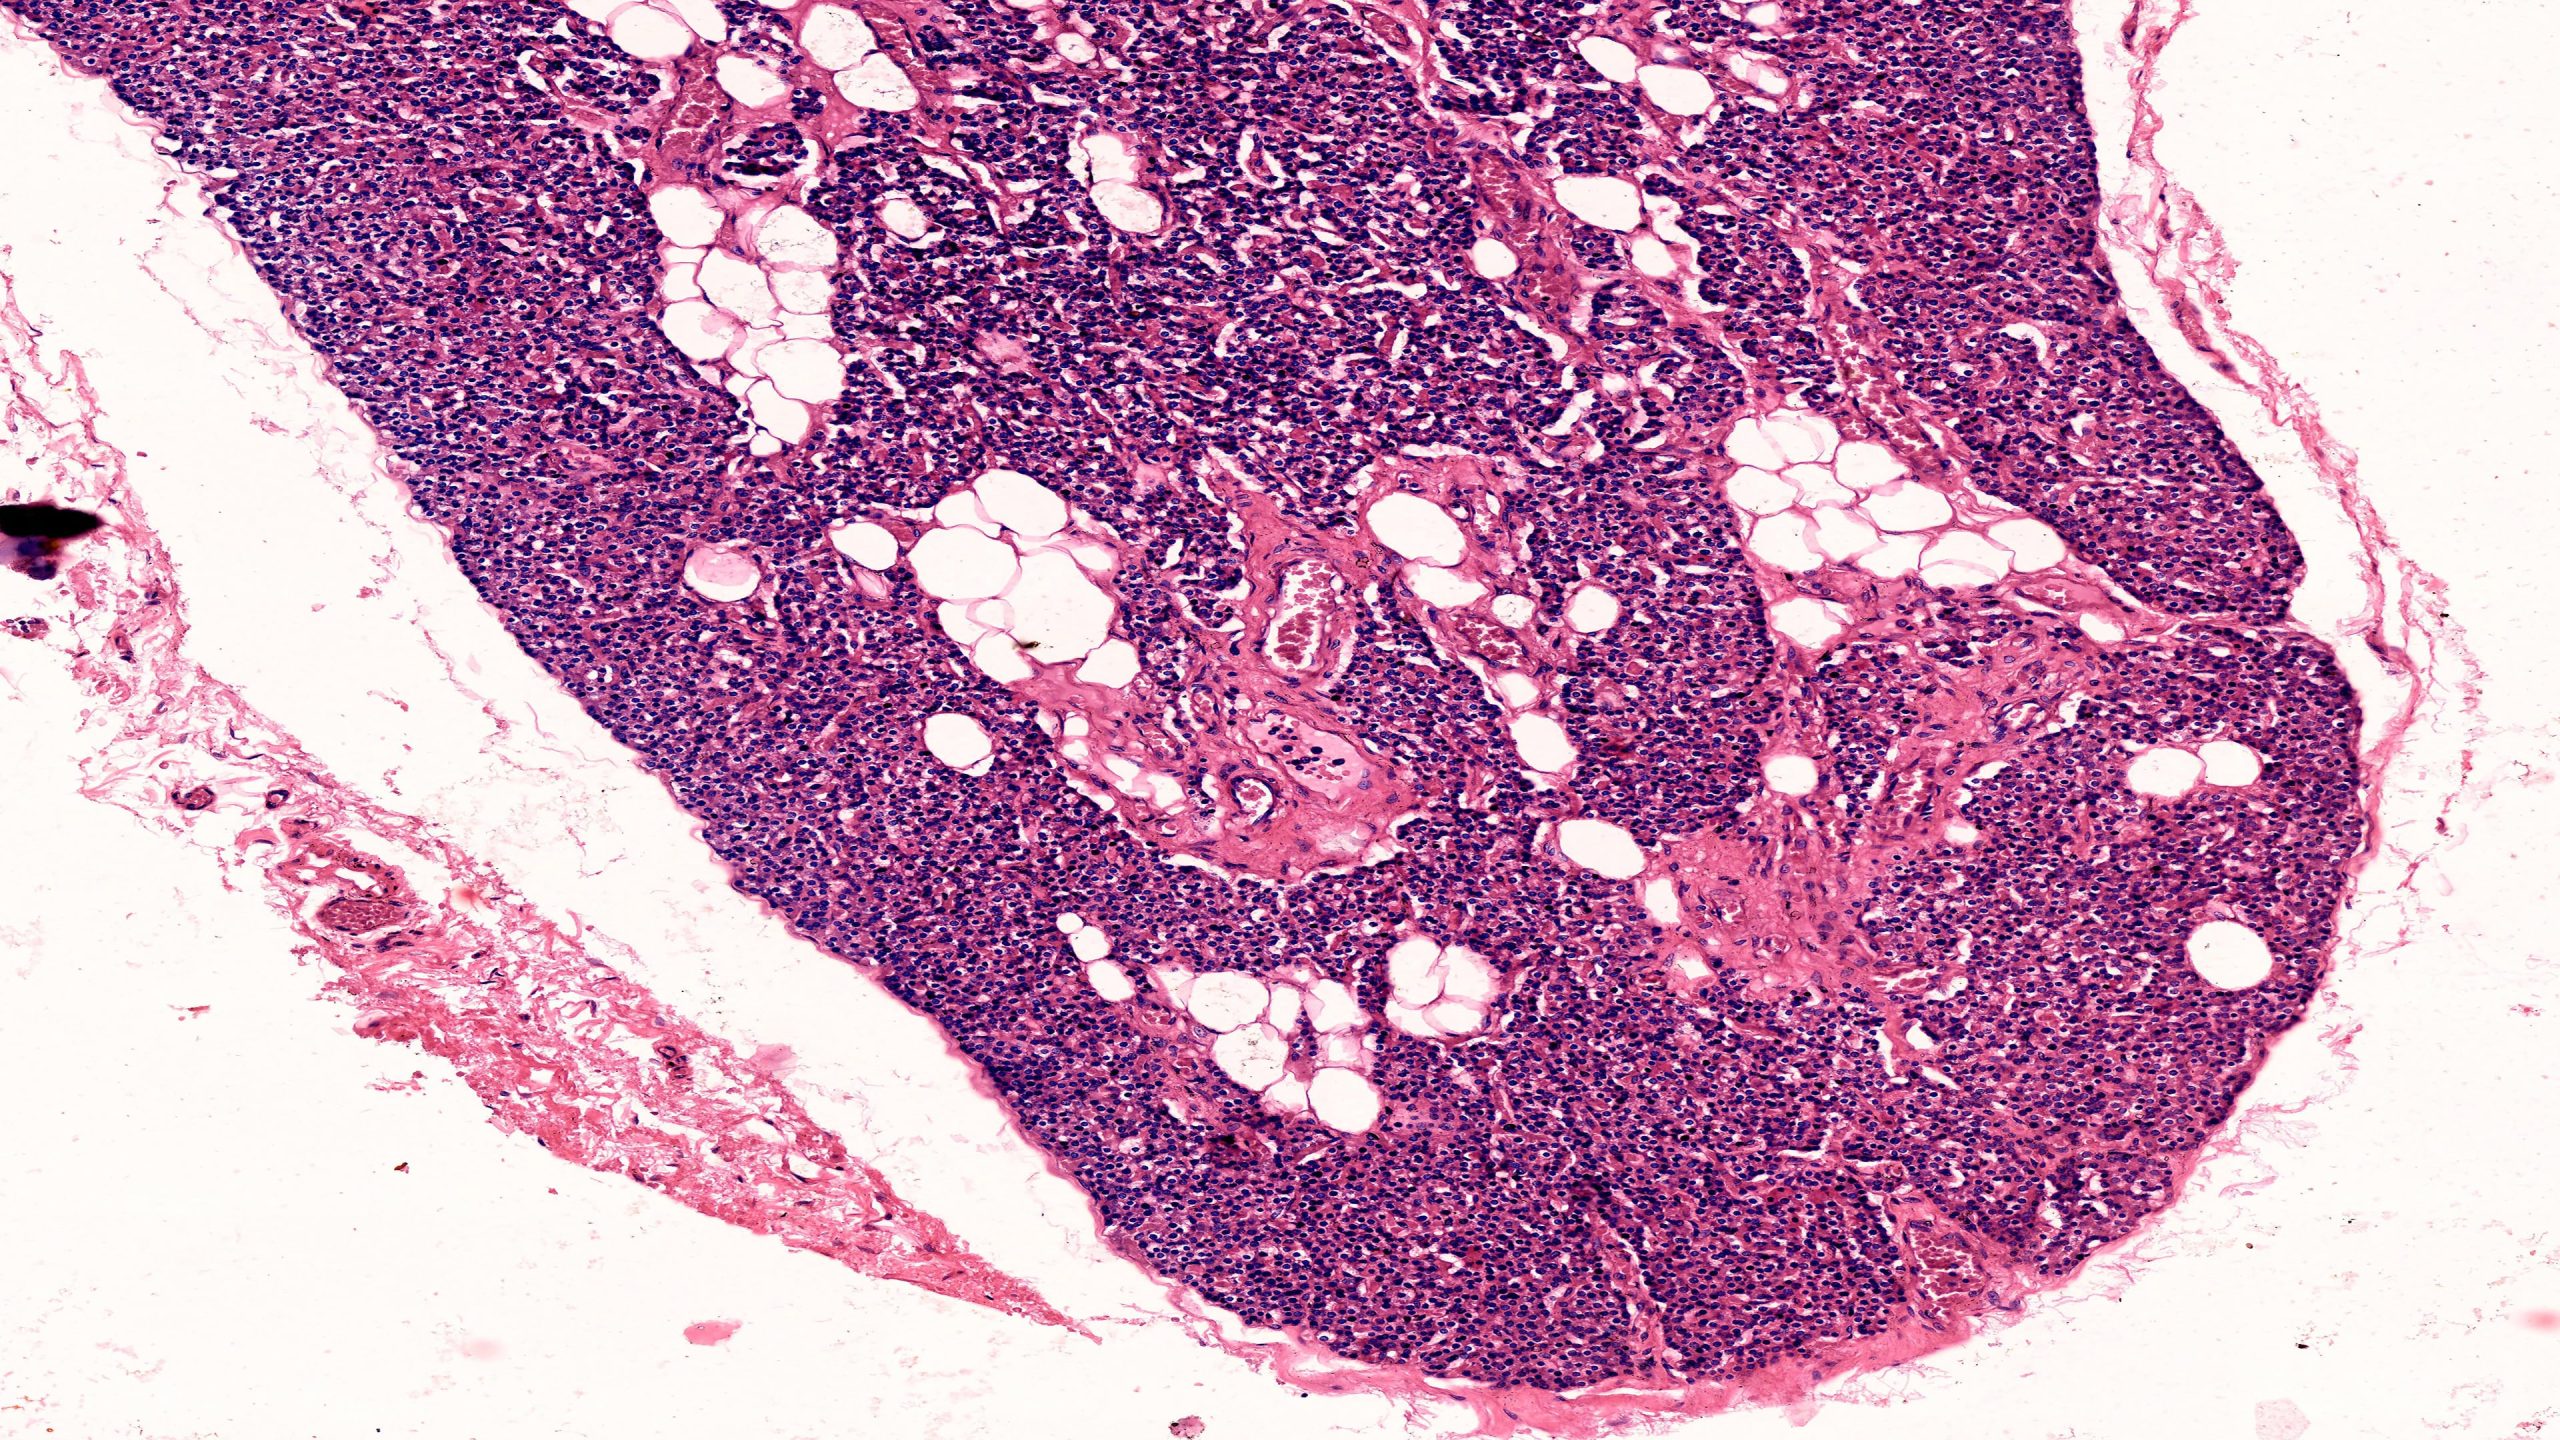

Thyroid and Parathyroid 10X